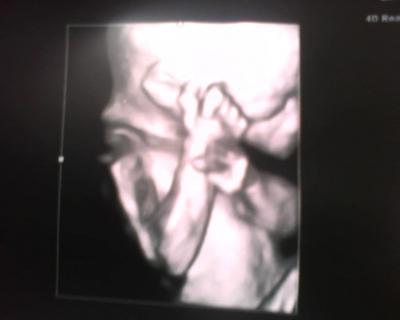

Und es wird....... ein Kopfkratzkrümel

Bild zu Mädels: Babynews! - Baby Forum - Allgemeine Themen

Hi sieht aus als ob die oder der mit ihrer oder seiner hand schmust,voll schön. lg